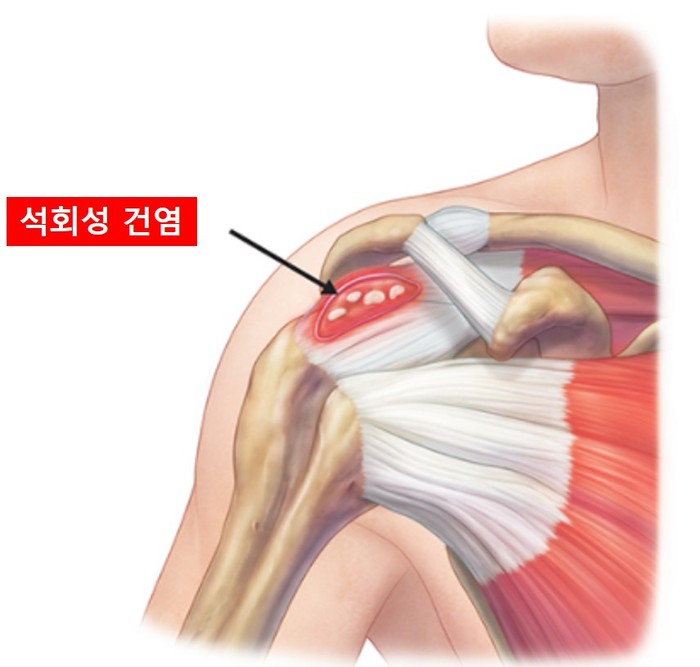

석회성건염

[Calcific tendinitis]

석회화를 동반하는 건의 염증

석회성건염은 칼슘 퇴적물이 힘줄에 침윤된, 자기 국한성의 통증을 동반하는 질병이다. 석회성건염은 우리 몸의 어느 힘줄에도 나타날 수 있지만, 대부분 어깨 관절의 극상건에서 발생하여 염증 및 통증을 야기하게 된다. 30세 이상에서 주로 나타나게 되며, 여성에서 남성보다 발생 빈도가 높다.

석회성 건염의 원인은 현재까지 명확하지 않지만, 힘줄의 퇴행성 변화, 미세 혈류의 감소 등이 이야기되고 있다.

석회성건염 환자들의 주 증상은 극심한 통증이며, 갑자기 발생하는 경우가 많다. 하지만 통증이 없는 경우도 많으며, 통증이 있는 경우에도 석회때문이 아닌, 다른 원인(충돌증후군, 유착성 관절낭염 등)에 의하여 발생하는 통증인 경우가 많다. 석회성건염은 전석회화시기, 석회화시기, 후석회화시기 총 3개의 단계로 나눌 수 있으며, 이 중 석회화 단계의 흡수기에 통증이 가장 심하게 된다.